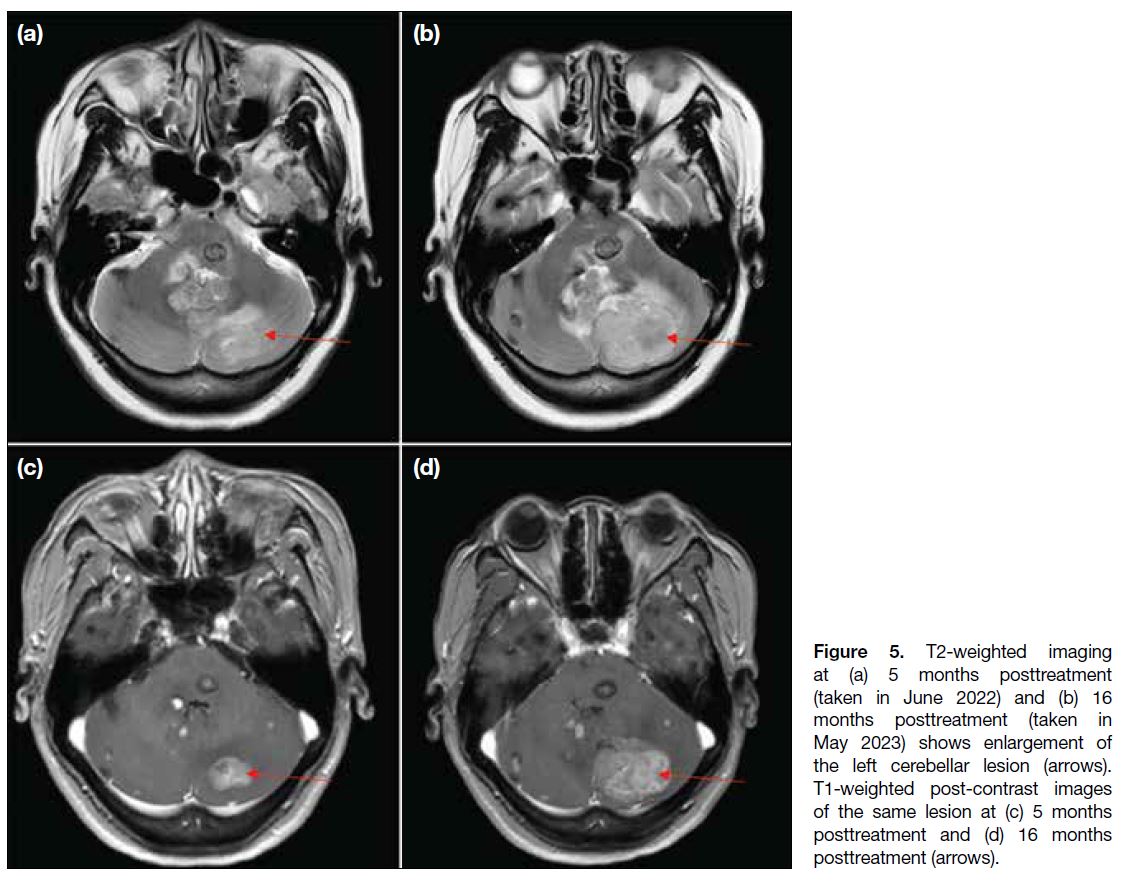

A further course of antiparasitic treatment was given,

assuming the infection was unresolved. Nonetheless,

follow-up scan at 16 months after initiation of antiparasitic

treatment showed not only persistent lesions, but interval

enlargement of some (the largest at the left cerebellar

hemisphere; Figure 5), with developing obstructive

hydrocephalus. In view of the patient’s worsening

symptoms of increased intracranial pressure (headache, dizziness and vomiting), as well as imaging findings,

the neurosurgical team intervened and left posterior

craniotomy was performed for decompression and to

excise the left cerebellar lesion. An external ventricular

drain was placed. Intraoperative findings noted a large

intra-axial tumour at the left cerebellar hemisphere,

likely malignant. Pathology confirmed a grade 3

neuroendocrine tumour, with additional comment that

Figure 5. T2-weighted imaging

at (a) 5 months posttreatment

(taken in June 2022) and (b) 16

months posttreatment (taken in

May 2023) shows enlargement of

the left cerebellar lesion (arrows).

T1-weighted post-contrast images

of the same lesion at (c) 5 months

posttreatment and (d) 16 months

posttreatment (arrows).